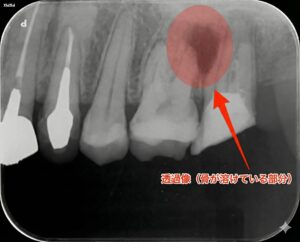

すぐにお話を伺い、レントゲン撮影を行いました。 すると、痛みを訴えている歯の根っこの先に、黒い影がはっきりと写っていました。

診断名は「急性根尖性歯周炎(きゅうせいこんせんせいししゅうえん)」。

これは、歯の根の中の神経が死んで腐ってしまったり、過去に治療した歯の中に細菌が繁殖したりすることで、根の先に急激に膿(うみ)が溜まってしまう病気です。